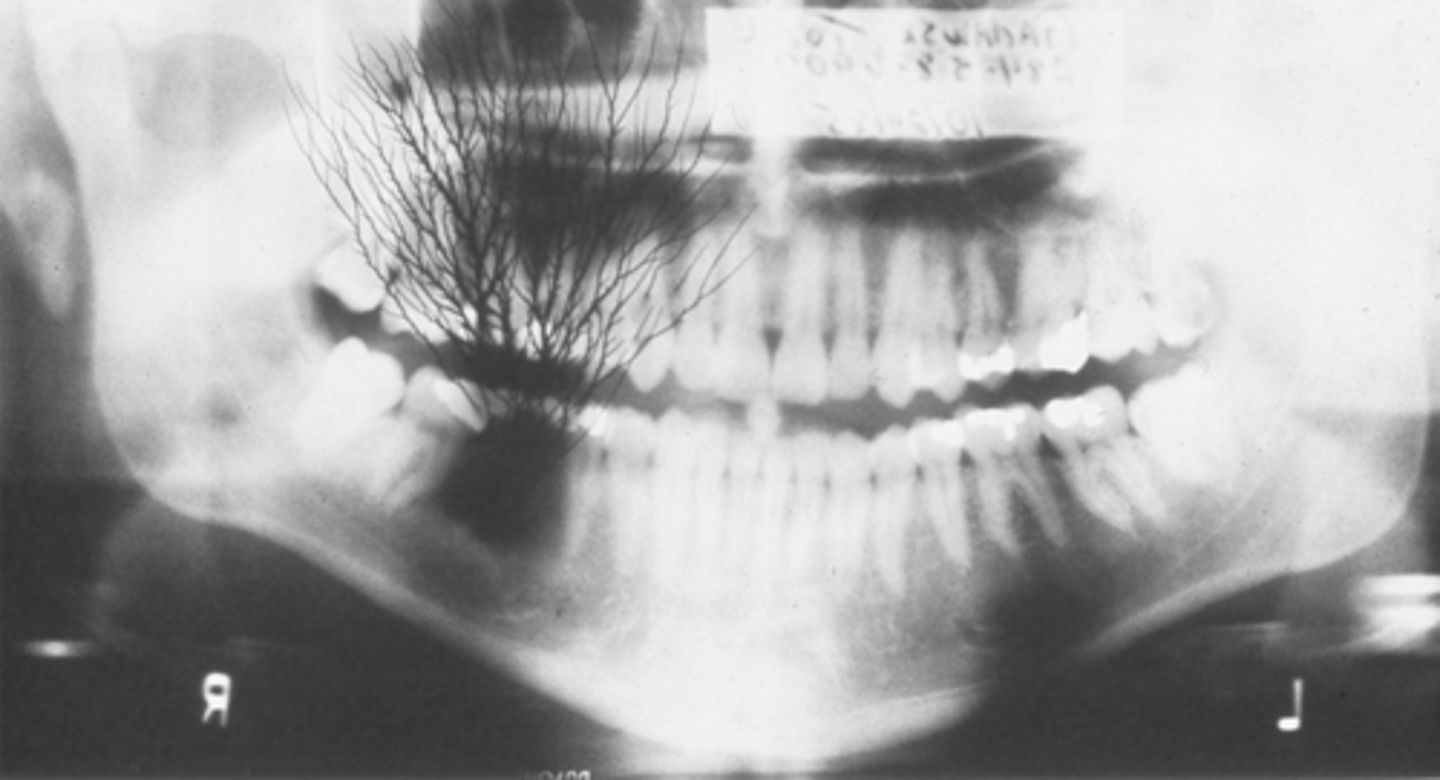

complete denture

waters projection